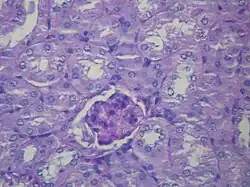

| Microscopic image of diabetic glomerulosclerosis, the main cause of nephrotic syndrome in adults. | |

- Focal segmental glomerulosclerosis (FSGS): is the most common cause of nephrotic syndrome in adults.[22] It is characterized by the appearance of tissue scarring in the glomeruli. The term focal is used as some of the glomeruli have scars, while others appear intact; the term segmental refers to the fact that only part of the glomerulus is damaged.